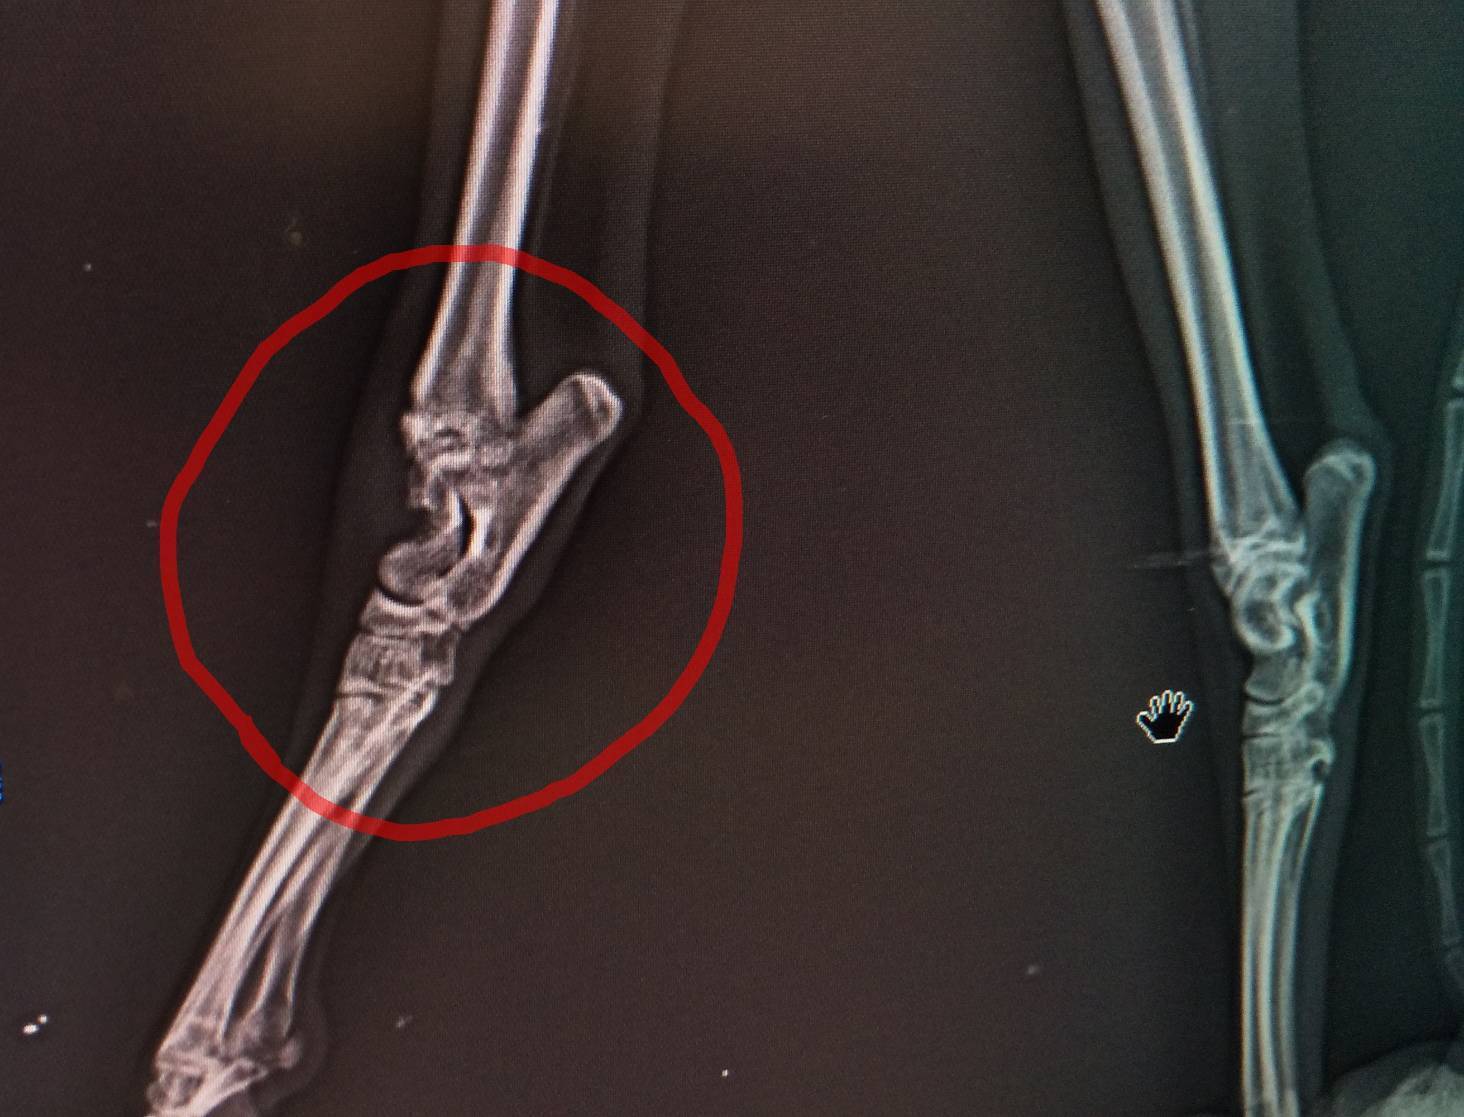

レントゲン①

割れた大腿骨付け根が神経とか筋肉密集エリアに刺さっているそうです。

それは聞いただけでも痛そうな状態。

矢印の部分を削る手術だそうです。